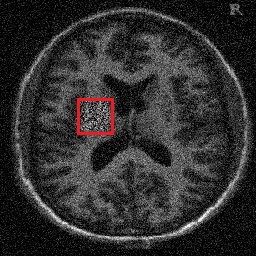

4.3. Large training set

As can be seen in the experiments with one training image, the spatially adapted does not only capture inhomogeneities in the noise, but also adapts to the scale of structures in the underlying image. Learning one fixed parameter, therefore, for more than one image seems counterintuitive since these local adaptions will change in each image. In the following experiment we argue, however, that if the training set features images with sufficiently similar content as well as with similar and heterogenous noise properties, as might be the case for MRI scans of brains, then the learned, spatially-adapted still outperforms a learned that is constant. To verify this, we compute the optimal functional parameter from a training set of 10 pairs , . The images (of size ) were taken from the OASIS online database. A Gaussian noise with was distributed on the images, and in the areas marked by red, additional noise with was imposed (to all noisy images at the same location).

The parameter values used for this experiment were , , and . We utilized the optimized Schwarz method , with overlapping size , and stop after two iterates. A total amount of 24 subdomains were considered and the computations were carried out in parallel. The semismooth Newton method, within each step of , stops whenever . The results are shown in Figure 4.7.

![]() |

The performance of the overall algorithm for the cases of 4 and 24 subdomains is registered in Table 4.2. It becomes clear from the data, that there is a significant decrease in the total computing time, when an increasing number of subdomains is considered. This, on the other hand, does not significantly affect the quality of the obtained image, measured by SSIM. We denote , , and are subdomains.